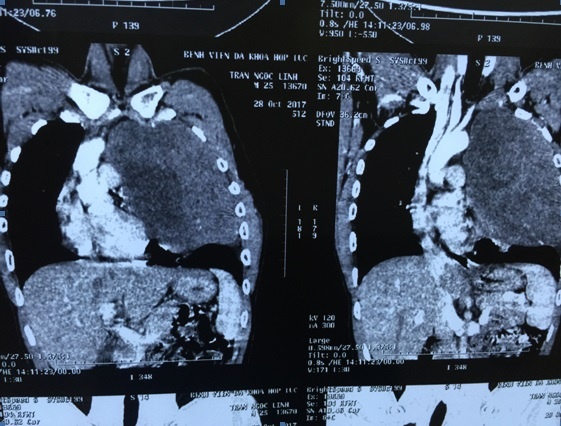

Sau khi làm các thủ tục chụp chiếu, xét nghiệm bệnh nhân được chẩn đoán u thần kinh trung thất trên trái. Hình ảnh khối u trung thất trên trái đường kính lớn 20x16 cm tỷ trọng mô mềm ngấm thuốc cản quang không đều, hoại tử một số vùng. Kết quả sinh thiết kim chẩn đoán giải phẫu bệnh kết luận u xơ thần kinh lành tính.

| Khối u với kích thước 20 x 16cm chiếm toàn bộ khoang lồng ngực. Ảnh: BVCC. |